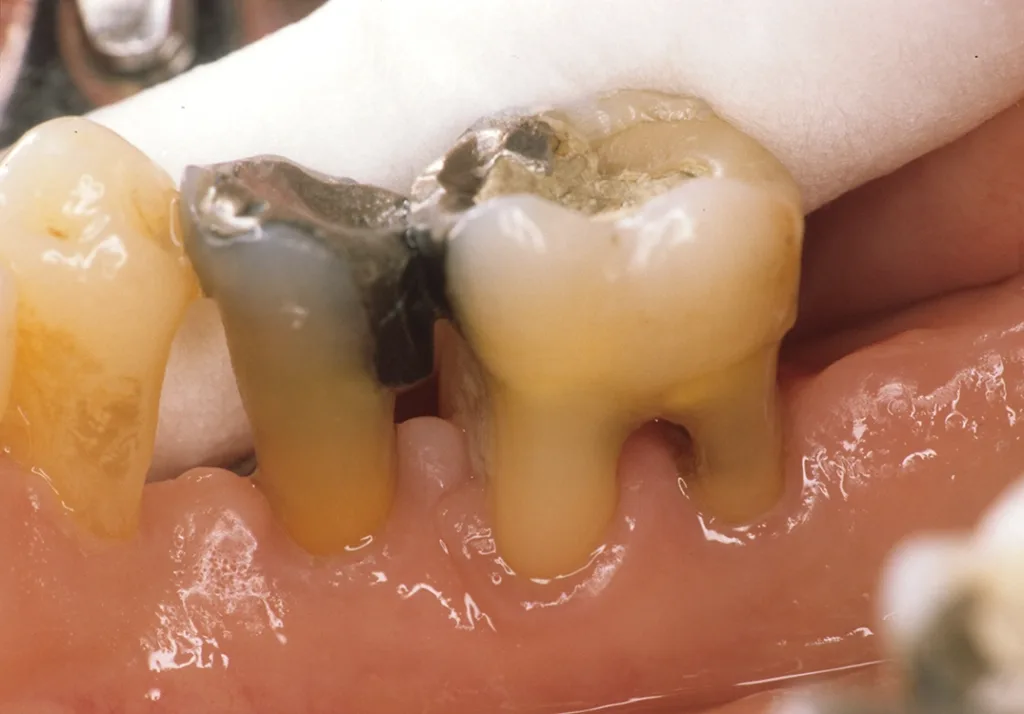

- Anatomie: Behandelte fortgeschrittene Parodontalerkrankungen sind klinisch stabil, zeigen aber in den implantatrelevanten anatomischen Knochenabschnitten (bukkale Lamellen, interapproximales Septum) weitere Abbauvorgänge durch Entzündung (Abb. 1 und 2) [1].

Daraus resultiert ein zweizeitiges Vorgehen mit (i) Entfernung prognostisch unsicherer Zähne, (ii) parodontaler Zieltherapie zur Sicherung des Restzahnbestandes, ergänzt durch (iii) mikrochirurgische Revision tiefer Resttaschen vor Implantation zum weiteren Entzündungsschutz (Abb. 3 und 4). Die Implantatplanung bleibt vorläufig. Ein definitiver Kostenvoranschlag wird erst nach funktioneller Entlastung und digitaler Beurteilung der Implantatknochenanatomie erstellt.